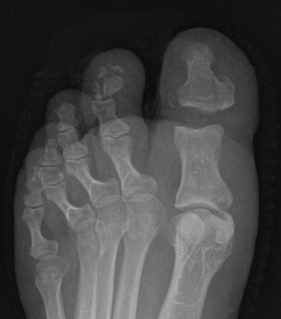

Great toe MTPJ dislocation

Xray

Blocks to closed reduction

Capsule / plantar plate

Sesamoids

Inter-sesamoid Ligament